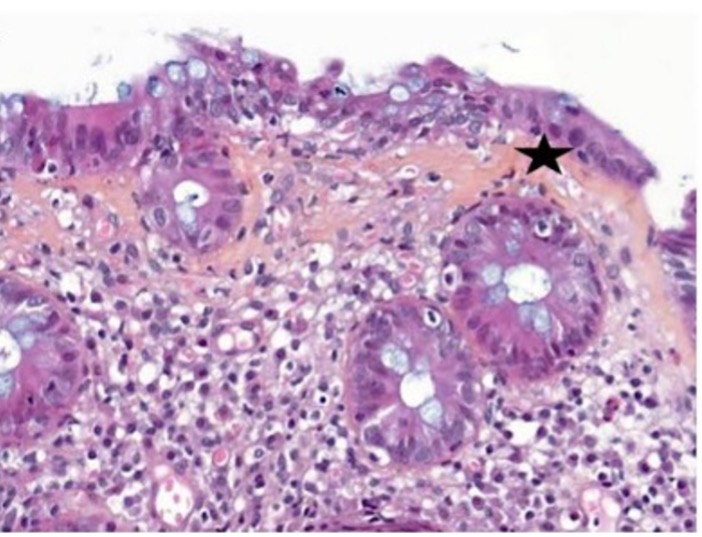

Comme dans le colon, elles diffèrent en fonction du type d’ICI. Dans tous les cas, une hépatite lobulaire avec une nécrose ponctuée est observée [Figure 3]. Les hépatites avec nécrose confluente centro-lobulaire ou pan-lobulaire sont plutôt observées sous anti-CTLA-4. C’est également le cas des hépatites microgranulomateuses et des granulomes à anneau de fibrine.

[Figure 3]

Hépatites lobulaires observées chez des patients traités par anti-CTLA-4 et/ou anti-PD-1

A. Hépatite microgranulomateuse (HES x120)

B. Hépatite avec des granulomes à anneau de fibrine (HES x370)

C. Hépatite lobulaire non granulomateuse (HES x190)

D. Hépatite portale et lobulaire avec endothélite (HES x190)

Comme illustré par la figure 3, les hépatites lobulaires présentent une nécrose ponctuée, un infiltrat lymphocytaire et histiocytaire, surtout intrasinusoïdal, et un infiltrat portal avec une discrète activité périportale et une endothélite veineuse portale. Pas ou peu de plasmocytes. Elles ne ressemblent pas à des hépatites auto-immunes et sont composées principalement de lymphocytes CD8+ CD4+.